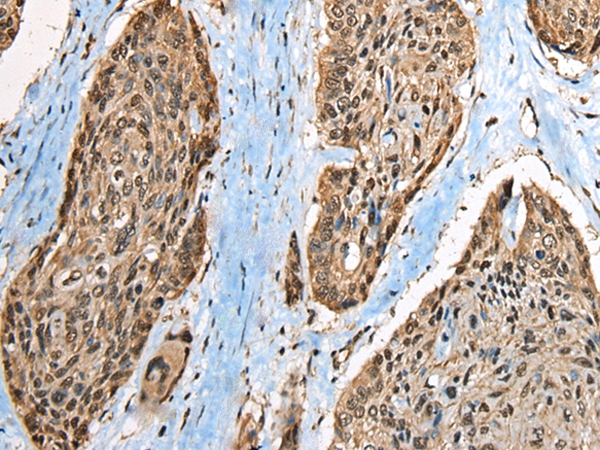

The image on the left is immunohistochemistry of paraffin-embedded Human esophagus cancer tissue using 46419(CCDC137 Antibody) at dilution 1/35, on the right is treated with fusion protein. (Original magnification: x200)